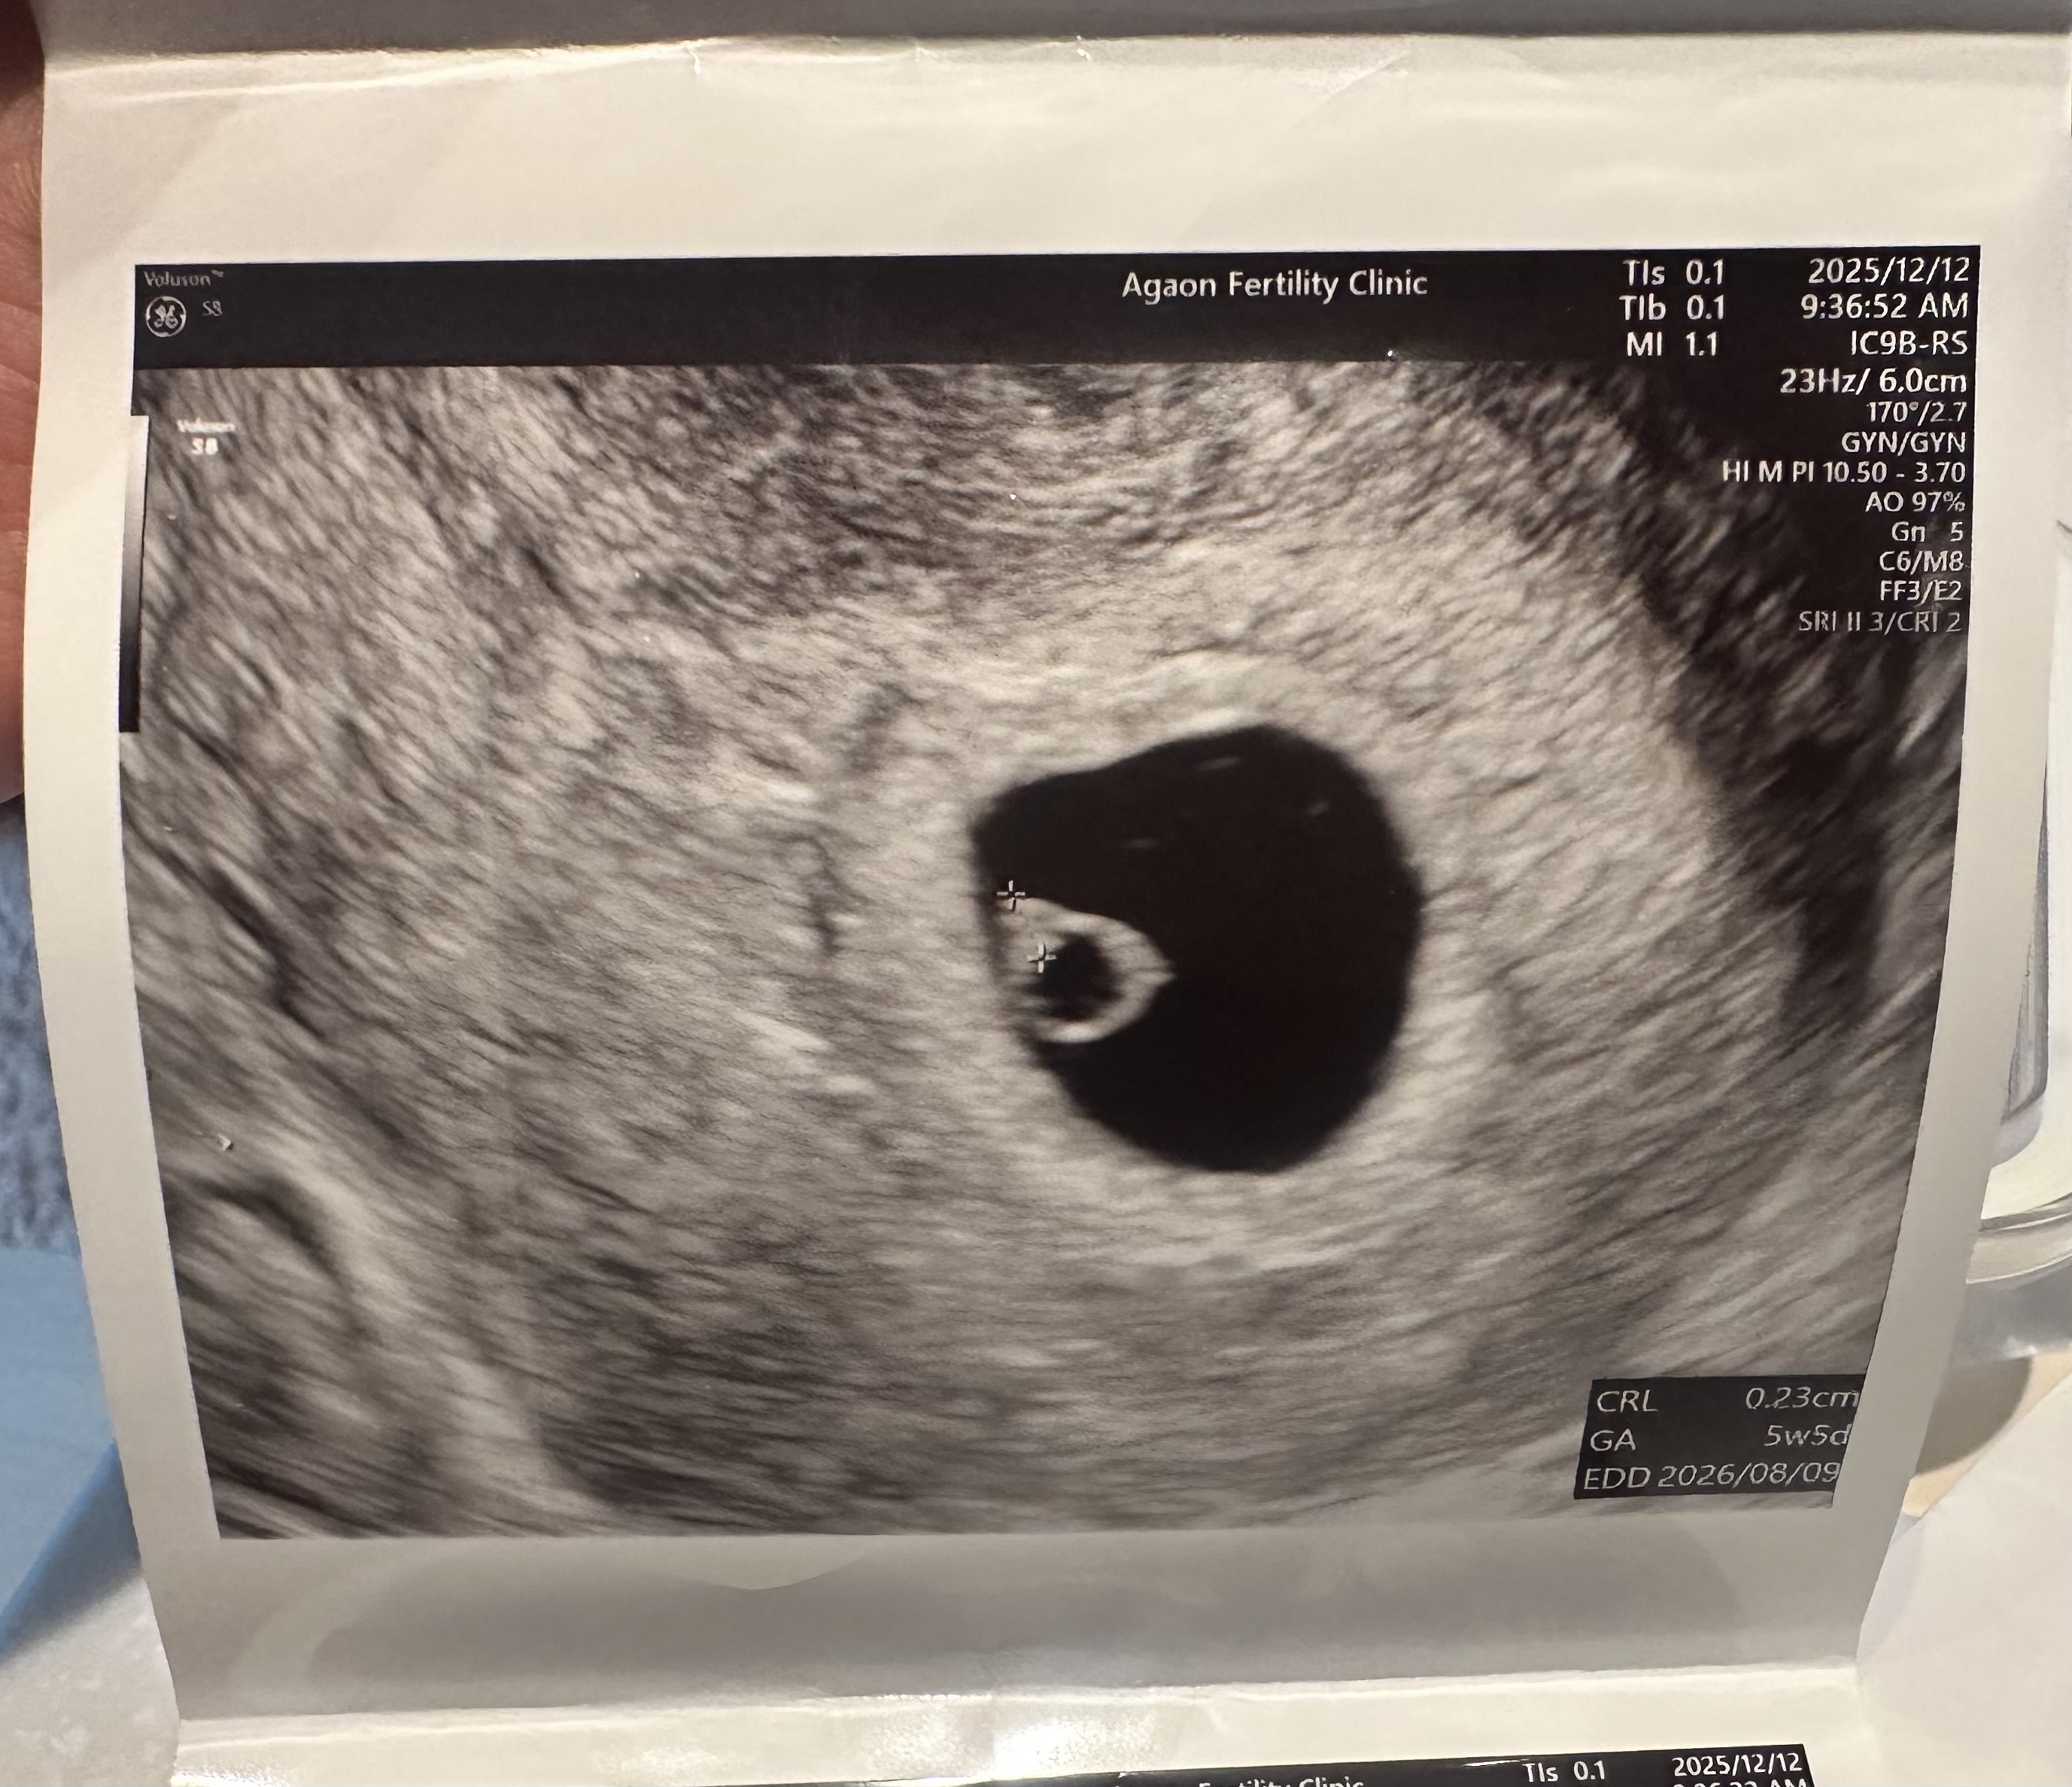

5주 4일 처음 초음파 봤어요!

심장뛰는걸 초음파로 보여주시는데 너무 신기했어요 :)